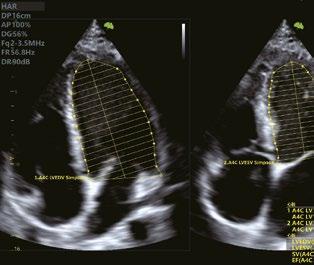

Apikale 4-Kammer-Ansicht zeigt segmentale und globale longitudinale Dehnung des linken Ventrikels

Mit einem Klick die Auswurfrate (EF) automatisch berechnen.